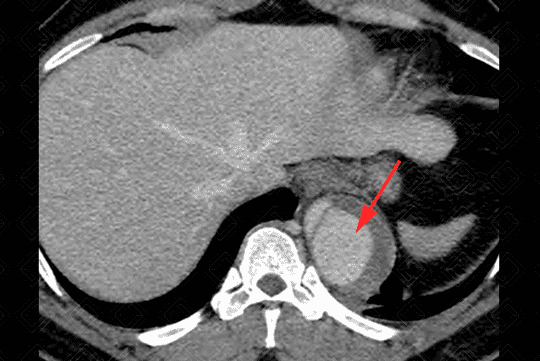

Descrição das imagens: Extensa dissecção da aorta descendente com dilatação da luz falsa (setas vermelhas) e redução das dimensões da luz verdadeira (asteriscos). É importante detalhar o suprimento dos ramos aórticos, ou seja, se estão sendo supridas pela falsa ou verdadeira luz. Neste paciente, observamos que a artéria renal esquerda (seta branca) está sendo suprida pela falsa luz (seta vermelha).

• Figura 2: Definir luz falsa e verdadeira: a luz com frequência tem área transversal maior devido ao fluxo lento. Sendo assim, a luz verdadeira está comprimida em cerca de 80% dos casos. Outro dado: a luz falsa é mais propensa à trombose;